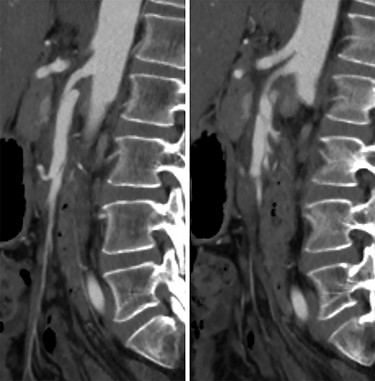

A 52-year-old woman presented to the emergency department with 3 days of diffuse abdominal pain that started during a dance class. The pain had a sudden onset with radiation to her back and did not worsen with meals. She had mild associated nausea and bloating but no other symptoms including emesis, hematochezia, melena or diarrhea. Her medical history was notable for former smoking history (10 pack-years, quit 5 weeks prior to presentation), but she was otherwise healthy and was taking no medications. Her surgical history consisted of laparoscopic appendectomy and diagnostic laparoscopy for endometriosis, both of which occurred more than a decade prior to presentation. She was hemodynamically stable with systolic blood pressure ranging from 100 to 120 s mmHg, and her exam was notable for mild diffuse abdominal tenderness without evidence of peritonitis. Her complete blood count and basic metabolic panel were within normal limits, and a venous blood gas demonstrated no evidence of lactic acidosis. A computed tomography (CT) angiogram of the abdomen and pelvis demonstrated a 5–6 cm length proximal SMA dissection with high-grade stenosis of the true lumen as well as a short-segment right external iliac artery dissection with mild narrowing of the true lumen (Fig. 1). There was no radiographic evidence of bowel ischemia.

CT angiogram of the SMA dissection demonstrating the Left: false lumen supplying the middle colic artery with Right: the narrowed true lumen supplying the other SMA branches.